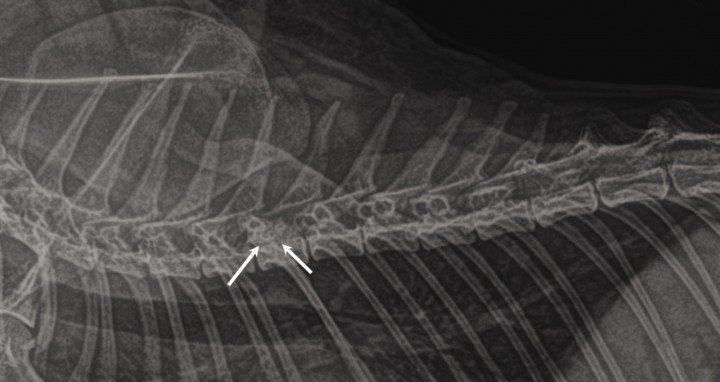

Las radiografías obtenidas de la columna torácica y lumbar demostraron esclerosis y proliferación ósea en la vértebra T6, con posible afección del canal vertebral (incremento de radiodensidad a nivel de T6) (Fig. 1). Seguidamente se procedió a la realización de una resonancia magnética (RM) de la columna torácica y lumbar en la que se evidenció una lesión que ocupaba el espacio epidural, hipointensa en secuencias T2W e isointensa en secuencias T1W en relación con la sustancia gris medular. Esta lesión manifestaba mínimo realce tras la administración de contraste endovenoso y se originaba a partir del cuerpo vertebral de T6, del que se diferenciaba difícilmente, ocupando el aspecto ventrolateral izquierdo del canal vertebral y produciendo una compresión severa del cordón medular (Fig. 2). Dada la escasa resolución y detalle de las alteraciones óseas se procedió a la realización de una tomografia computarizada (TC) tras la administración de contraste intratecal (mielo-TC) en la que se observaron extensos fenómenos osteoproliferativos centrados en el cuerpo y pedículo izquierdo de T6 que invadían el aspecto ventrolateral izquierdo del canal vertebral induciendo una desviación severa del cordón medular (Fig. 3). La lesión producía un patrón compresivo extradural con atenuación del anillo de contraste. No se evidenciaron signos de reacción perióstica pero sí pequeñas áreas puntiformes radiolúcidas en el hueso neoformado (Fig. 3B). Previamente a la inyección de contraste intratecal se obtuvo una muestra de líquido cefalorraquídeo que no reveló alteraciones ni en el recuento ni en el tipo celular. El diagnóstico radiológico fue el de una lesión ósea focal que ocupaba el espacio epidural, originada a partir del cuerpo de T6 con compromiso medular severo cuyos diagnósticos diferenciales incluyeron osteomielitis, granuloma inflamatorio, neoplasia ósea, neoformación ósea como consecuencia de traumatismo previo o malformación vascular ósea.

<p>Radiografía lateral de la columna torácica en la que se aprecia una lesión osteoproliferativa que afecta al cuerpo vertebral de T6 con aumento de opacidad en el canal vertebral a este nivel (flechas).</p>

Radiografía lateral de la columna torácica en la que se aprecia una lesión osteoproliferativa que afecta al cuerpo vertebral de T6 con aumento de opacidad en el canal vertebral a este nivel (flechas).